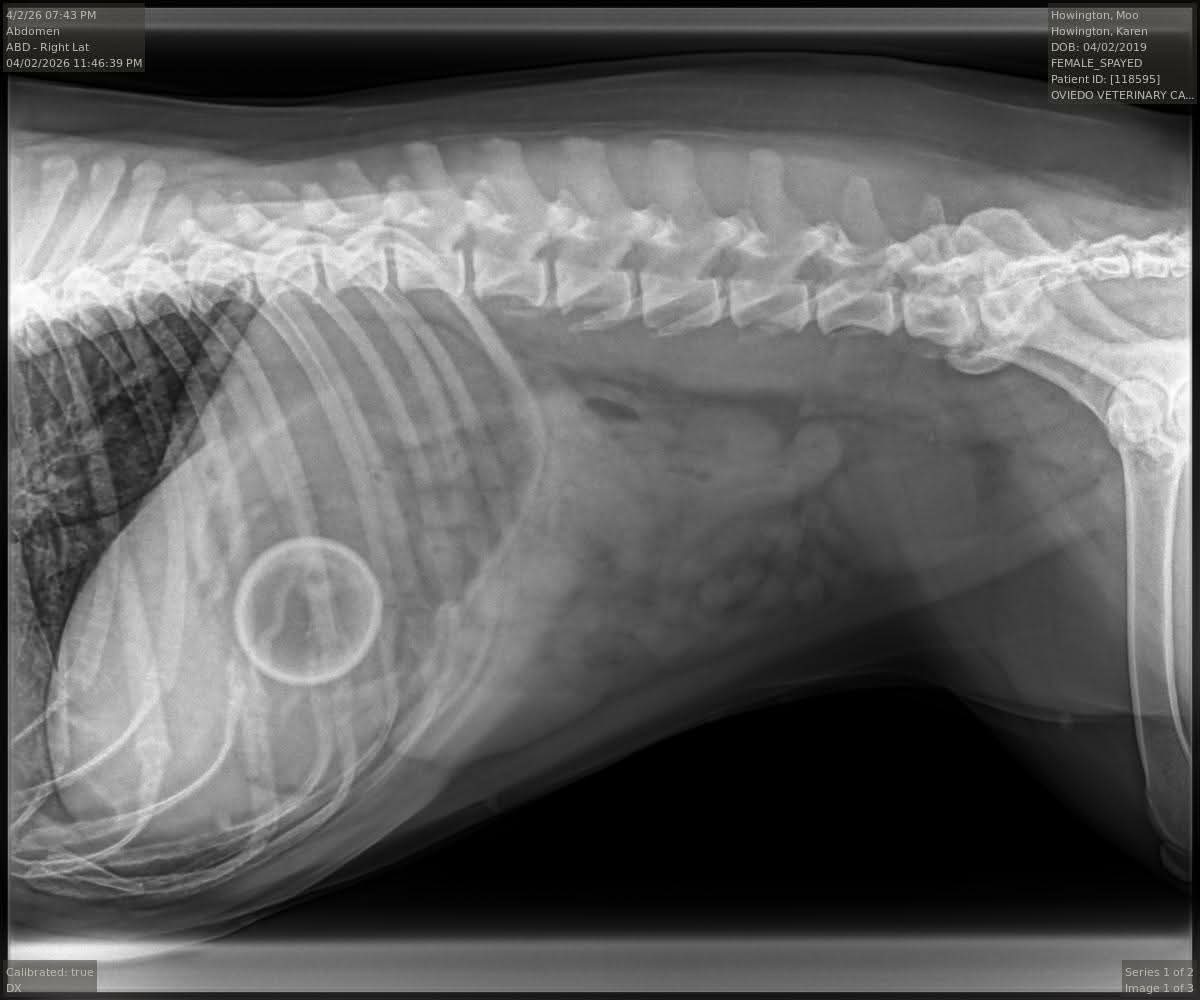

Moo is our first beautiful dog and my soul baby. A rescue we got at the local shelter 6 years ago when she was just a year old. She is full of more love and silly goofy light than anyone could imagine. Even through her worst times she has the biggest smile on her face and is wagging her crooked tail. Over the weekend, Moo got sick out of nowhere. She was consistently vomiting and was taken to the vet for testing, all of which came back completely healthy. After we thought she started feeling better and assuming it was stress from our recent move, Moo rapidly declined and got very sick again over the course of hours. After X-rays, an obstruction was found in Moos stomach and she is getting emergency surgery to remove it. She is very likely to recover which is a major relief we are so beyond grateful for, but we must pay $8500 by tonight in order for them to operate. As we are getting married this year and just moved, much of our funds had been allocated to that. We are asking for help from our community to help us get Moo through this as she is more important to us than anything. We are so appreciative of any help and look forward to sharing her recovery and getting her healed. Thank you.